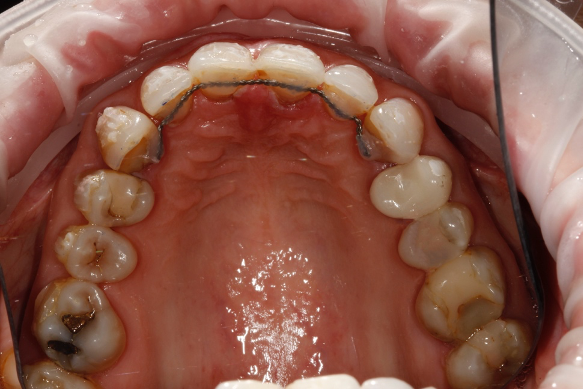

The treatment time in fixed orthodontics was 2.5 months. This focused mainly on the maxillary anterior teeth. Dual arch fixed orthodontic appliances were placed. Mainly to allow for use of additional elastics to expedite finishing. Elastics were also used within the upper arch to redistribute space to further minimise invasiveness by reducing the reliance upon IPR (Figure 3).

Post orthodontically, the patient had fixed and removable retainers provided. The patient is educated from the very start that this will be a lifelong commitment for them (Figures 4a and b).